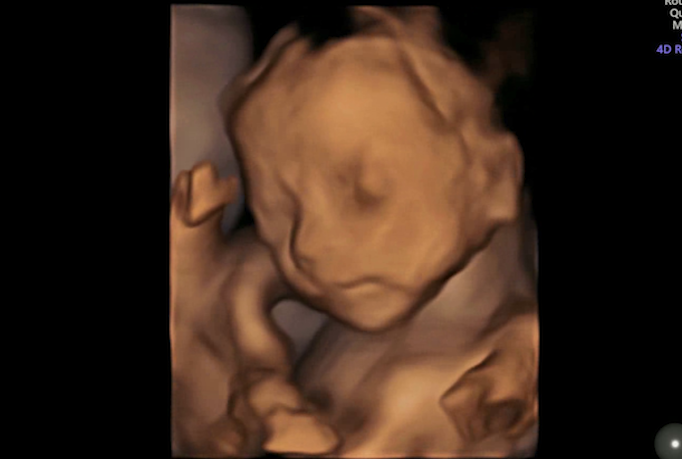

看到了宝宝的小模样